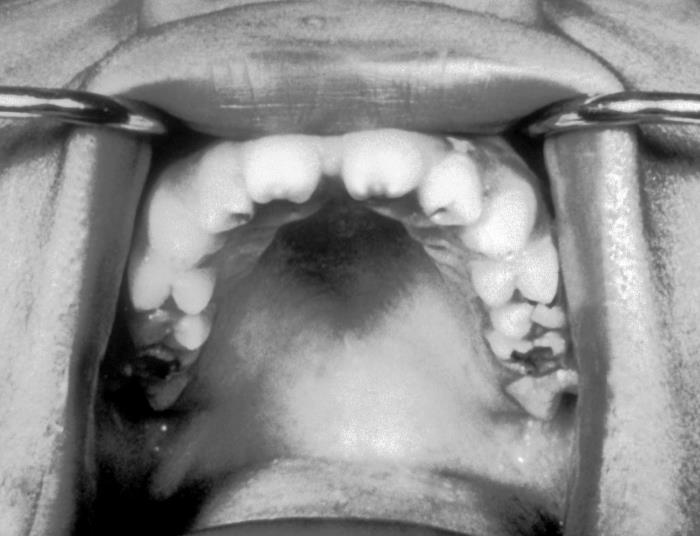

This photograph depicts an intraoral view of a patient’s mouth exposing the abnormalities associated with the dentition, known as Hutchinson’s teeth, which resulted from a congenital syphilis infection, by the bacterium, Treponema pallidum. Hutchinson’s teeth involves a narrowing, and notching of the teeth, imparting a screwdriver like shape to affected teeth, like these central incisors.